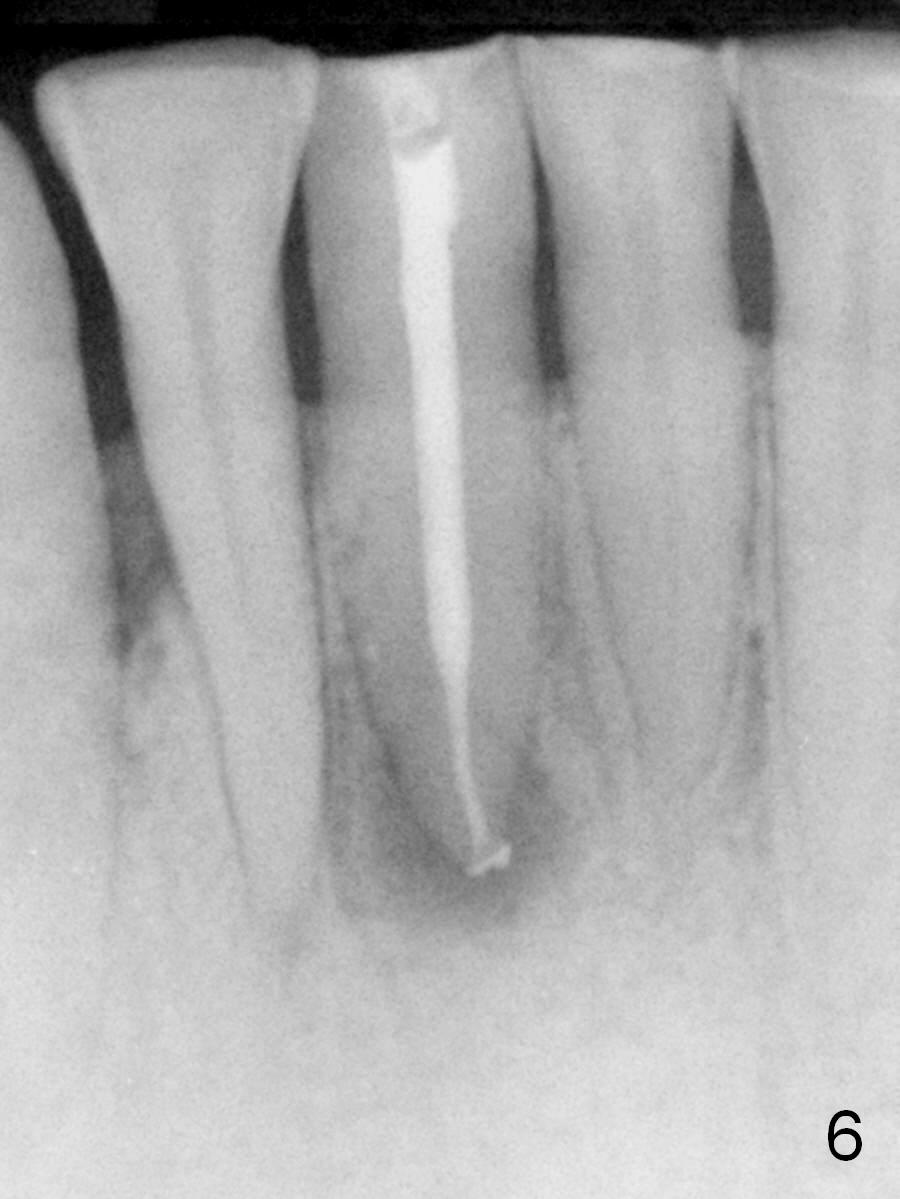

A 45-year-old man has had a chronic fistula associated with the tooth #25 (Fig.1). There is purulent discharge sometimes. After debridement with hand files #10-20 and rotary one 30/06, a master cone 30/.06 is inserted incompletely (Fig.2). After rotary files 30/.08 at 16.0 mm and 30/.10 at 15.0 mm and hand files 10-20 at 17 mm, the master cone is apparently inserted to the WL. With application of Endo Sequence Sealer (syringe), the master cone is reinserted (Fig.3). When the rubber dam is removed, the sealer is found to have expelled from the fistula. With an endo curette (Fig.5), the sealer is removed from the deepest portion of the sinus tract (apex of the tooth). What do you want to know the outcome of the supplementary surgical maneuver? The sealer is gone (Fig.6). The immediately supplementary treatment avoids a separate apicoectomy. No fistula is noted <2 weeks postop (Fig.7). The attrition is due to #8 and 9 veneers, fabricated 8 years earlier. The tooth #24 is symptomatic with loss of incisal composite nearly 4 years postop (Fig.8 <). After 30/.04 gutta percha (GP) try in (Fig.9), RCT is finished without accessory GP (Fig.10).